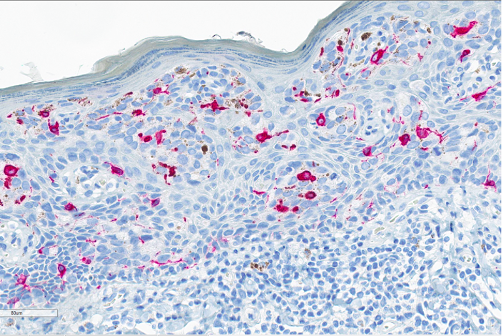

Figure 7. Immunohistochemistry. Melan-A, a cytoplasmic stain, was interpreted as negative in the cytoplasm of cells of interest but highlights the intraepithelial melanocytes.

In some cases, there may be melanin pigment throughout the epidermis and dermis, which gives rise to a melanoma differential. In this situation, SOX10 and Melan-A will stain the background melanocytes; however, the Paget tumor cells will be negative. Other differentials include vulvar intraepithelial neoplasia, HPV-independent (dVIN), high-grade squamous intraepithelial lesion (HSIL) with pagetoid spread, and secondary Paget disease. dVIN can microscopically look like Paget with the nested, pale tumor cells, as well as mucinous differentiation, however, it will be negative for CK7 and GCDFP-15. HSIL can mimic Paget with mucinous areas, melanin pigment, and pagetoid spread too. To best differentiate HSIL from Paget, high-risk HPV ISH is useful, as it will be positive in HSIL and negative in Paget. The last differential is secondary Paget, which is much less common and originates in another location before metastasizing, such as the rectum, cervix, or bladder. These would stain for CDX2, CK20, or uroplakin-3, respectively.